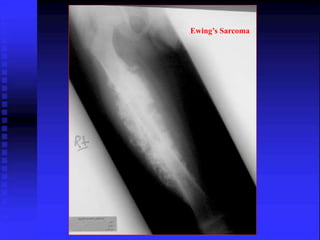

Ewing’s Sarcoma